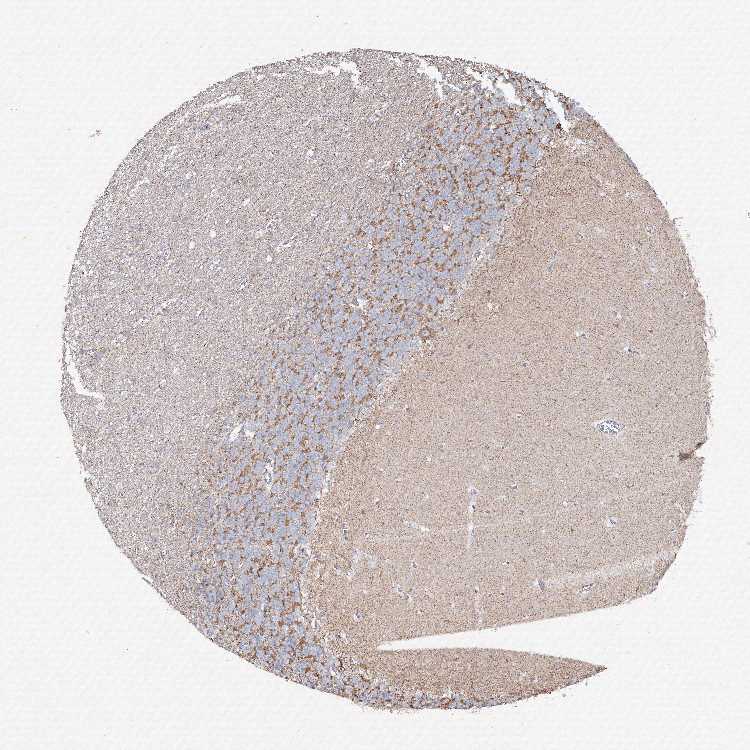

CEREBELLUM - Antibody stainingi

Antibody staining in the annotated cell types in the current human tissue is reported as not detected, low, medium, or high, based on conventional immunohistochemistry profiling in selected tissues. This score is based on the combination of the staining intensity and fraction of stained cells.

Each image is clickable and will lead to virtual microscopy that enables deeper exploration of all samples and also displays staining intensity scores, fraction scores and subcellular localization as well as patient and tissue information for each sample.

Antibody HPA037753

Purkinje cells Medium

Cells in granular layer Low

Cells in molecular layer Not detected